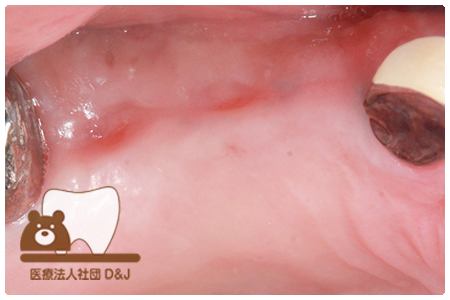

治療前

治療後

治療前

治療後

治療前

治療後

53歳 女性

- 治療内容

- 療内容奥歯にインプラントの埋入

- 治療期間

- 5ヶ月

- 費用

- 自費

インプラント体 1本:275,000円(税込)

インプラント上部構造(ジルコニア)2本:1本110,000円(税込)×2本=220,000円(税込)

(R8.3月時点)

- その他の治療の費用は含まれておりません。

- リスク・副作用

- インプラントは外科手術を伴うため、術後に腫れや痛み、出血、感染が生じることがあります。術後の指示を守らない場合、症状が悪化する恐れがあります。また、治療後に口腔内の清掃や定期的なメインテナンスを怠ると、インプラント周囲粘膜炎やインプラント周囲炎を引き起こすことがあり、インプラントの脱落につながる可能性があります。